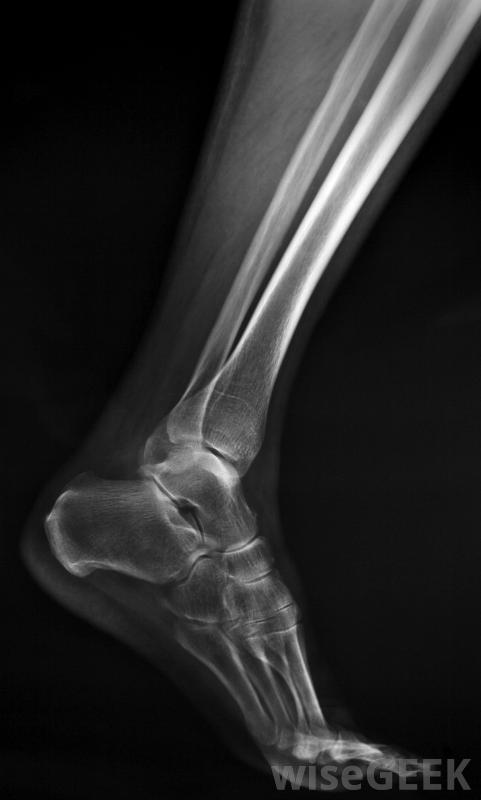

什么是踝關節融合術(Ankle Arthrodesis)?

踝關節融合術是一種將小腿脛腓骨和踝關節距骨的關節融合在一起的手術,這種手術通常用于治療嚴重的踝關節疼痛,通常是由關節炎引起的。它通常只適用于那些嘗試過非手術治療的患者,例如經過特殊改造的鞋子和止痛藥,但沒有成功。踝關節融合通常用于年輕、活動更活躍的患者,作為人工踝關節置換術的替代方案,因為融合的關節更多踝關節融合術是距骨與脛腓骨之間的關節融合的一種手術踝關節融合術包括將踝關節距骨與小腿脛骨和腓骨的末端固定在一起。在將骨頭表面整平以去除受損的骨和軟骨后,金屬螺釘是用來將它們固定在一起的。作為愈合過程的一部分,新骨的形成將切割面結合并融合關節。踝關節隨后變得僵硬,但腳和膝蓋的柔韌性有助于彌補這一點,盡管跑步可能無法進行,但患者通常能夠正常行走關節融合術后,通常需要三個月左右才能完成融合,因此關節需要休息,在此期間可能需要戴石膏踝關節融合術后,患者需要支撐石膏并使用拐杖。鎖孔手術可用于踝關節融合術,其優點是恢復更快,與傳統的開放式手術方法相比,術后疼痛減輕。在一種被稱為關節鏡的鎖孔手術技術中,在踝關節的皮膚上做一些小切口,以便將觀察儀器和微型手術工具一起插入關節。患者通常能夠在一天內將體重放在關節上手術后,使用支撐石膏或拐杖,并開始理療。開放手術可用于更復雜的病例,可能除了關節融合術外,還需要矯正畸形,有時會在腿部周圍固定一個外部金屬框架,以固定骨骼,而不是在關節內放置螺釘治療踝關節疼痛通常需要醫生的正確診斷踝關節融合術是指在融合的腳踝周圍的其他關節上施加額外的壓力,隨著時間的推移,可能會導致關節炎。對于一個患有兩個腳踝關節炎的人來說,如果兩個腳踝都融合在一起,可能會非常殘疾,因為從椅子上起來需要一定程度的踝關節柔韌性在這種情況下,關節置換可用于一個踝關節,對于不太活躍或年紀較大、不太可能磨損假體的人來說,踝關節活動性可能比關節穩定性更重要,而人工踝關節置換術可能是比踝關節融合術更好的選擇由于踝關節(由脛骨和距骨組成),腳能夠旋轉,與腓骨遠端一起。更復雜的踝關節融合術將是開放性手術,患者恢復時間較長。